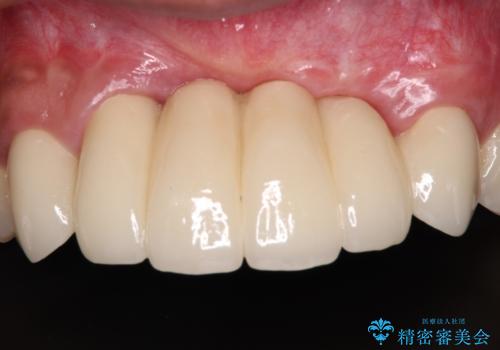

- ソーシャルメディアでのゲームに夢中になっている最中に車と接触し、前歯の抜歯を余儀なくされた患者様です。

初診時では前歯が保存できる可能性も模索しましたが、損傷が激しく3歯を抜去することとなりました。

保存となった隣在歯も神経が失活していており、補綴治療が必要であったので、オールセラミッククラウンにて補綴治療することとしました。